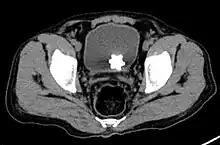

Large jackstone in the bladder of a 60-year-old man. Stone was removed by open cystolithotomy

The diagnosis of bladder stone includes urinalysis, ultrasonography, x rays or cystoscopy (inserting a small thin camera into the urethra and viewing the bladder). The intravenous pyelogram can also be used to assess the presence of kidney stones. This test involves injecting a radiocontrast agent which is passed into the urinary system. X-ray images are then obtained every few minutes to determine if there is any obstruction to the contrast as it is excreted into the bladder. Today, intravenous pyelogram has been replaced at many health centers by CT scans. CT scans are more sensitive and can identify very small stones not seen by other tests.[8]